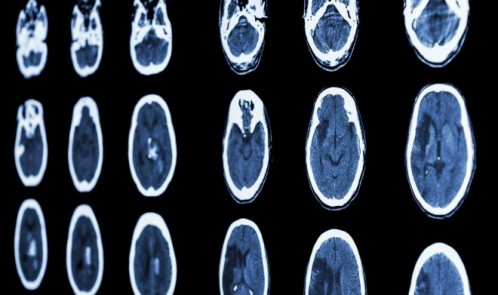

نوروسافاری| مصرف همزمان داروهای افسردگی با مُسکن‌های غیر استروئیدی همچون «ایبوپروفن» یا «ناپروکسن»، خطر خونریزی مغزی را افزایش می‌دهد.

به گزارش نوروسافاری به نقل از ایسنا، پزشکان کره‌ای در یک بررسی جدید دریافتند از بین بیش از چهار میلیون نفری که برای اولین بار داروی افسردگی برایشان تجویز شده بود، افرادی که همزمان از داروهای ضدالتهابی غیراستروئیدی نیز استفاده کرده‌ بودند ظرف یک ماه آینده بیشتر با خطر ابتلا به خونریزی مغزی داخل جمجمه‌ای مواجه شدند.

این نوع از خونریزی مغزی می‌تواند به آسیب‌دیدگی دائمی مغز یا حتی مرگ منجر شود. همچنین طبق اعلام سازمان غذا و داروی آمریکا، برخی از داروهای ضدالتهابی غیراستروئیدی که مسکن‌های غیرنسخه‌ای و پرمصرف هستند نیز می‌توانند خطر سکته مغزی و قلبی را افزایش دهند.